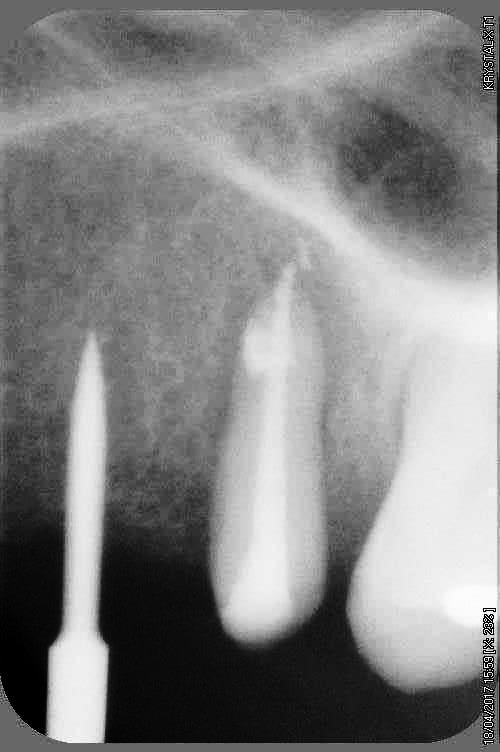

petit cas sympa ancien bridge très mobile....plutôt que d'extraire 25, j'ai déposé la couronne, retraité la dent stabilisation pendant deux mois puis séance d'ostéotension et ce jour pose de deux axioms PX 34120 après expansion...

Pas de preforage dans ce cas là, directement à l'osteotome demi lune

non, uniquement travail par voie crestale, très légère fêlure niveau 23, mais sans conséquence